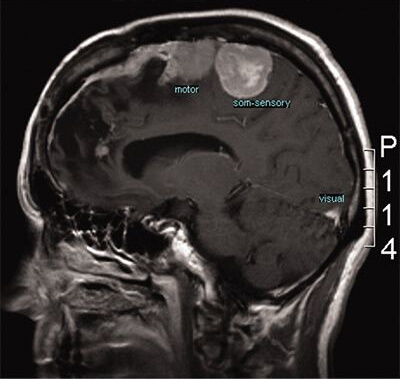

Hyperbaric Oxygen Therapy as a Complementary Treatment in Glioblastoma—A Scoping Review

Front Neurol. 2022; 13: 886603; Published online 2022 Jul 1. doi: 10.3389/fneur.2022.886603; PMCID: PMC9283648; PMID: 35847231

Hyperbaric oxygen therapy as adjunctive strategy in treatment of glioblastoma multiforme

Med Gas Res. 2018 Jan-Mar; 8(1): 24–28; Published online 2018 Apr 18. doi: 10.4103/2045-9912.229600; PMCID: PMC5937300; PMID: 29770193